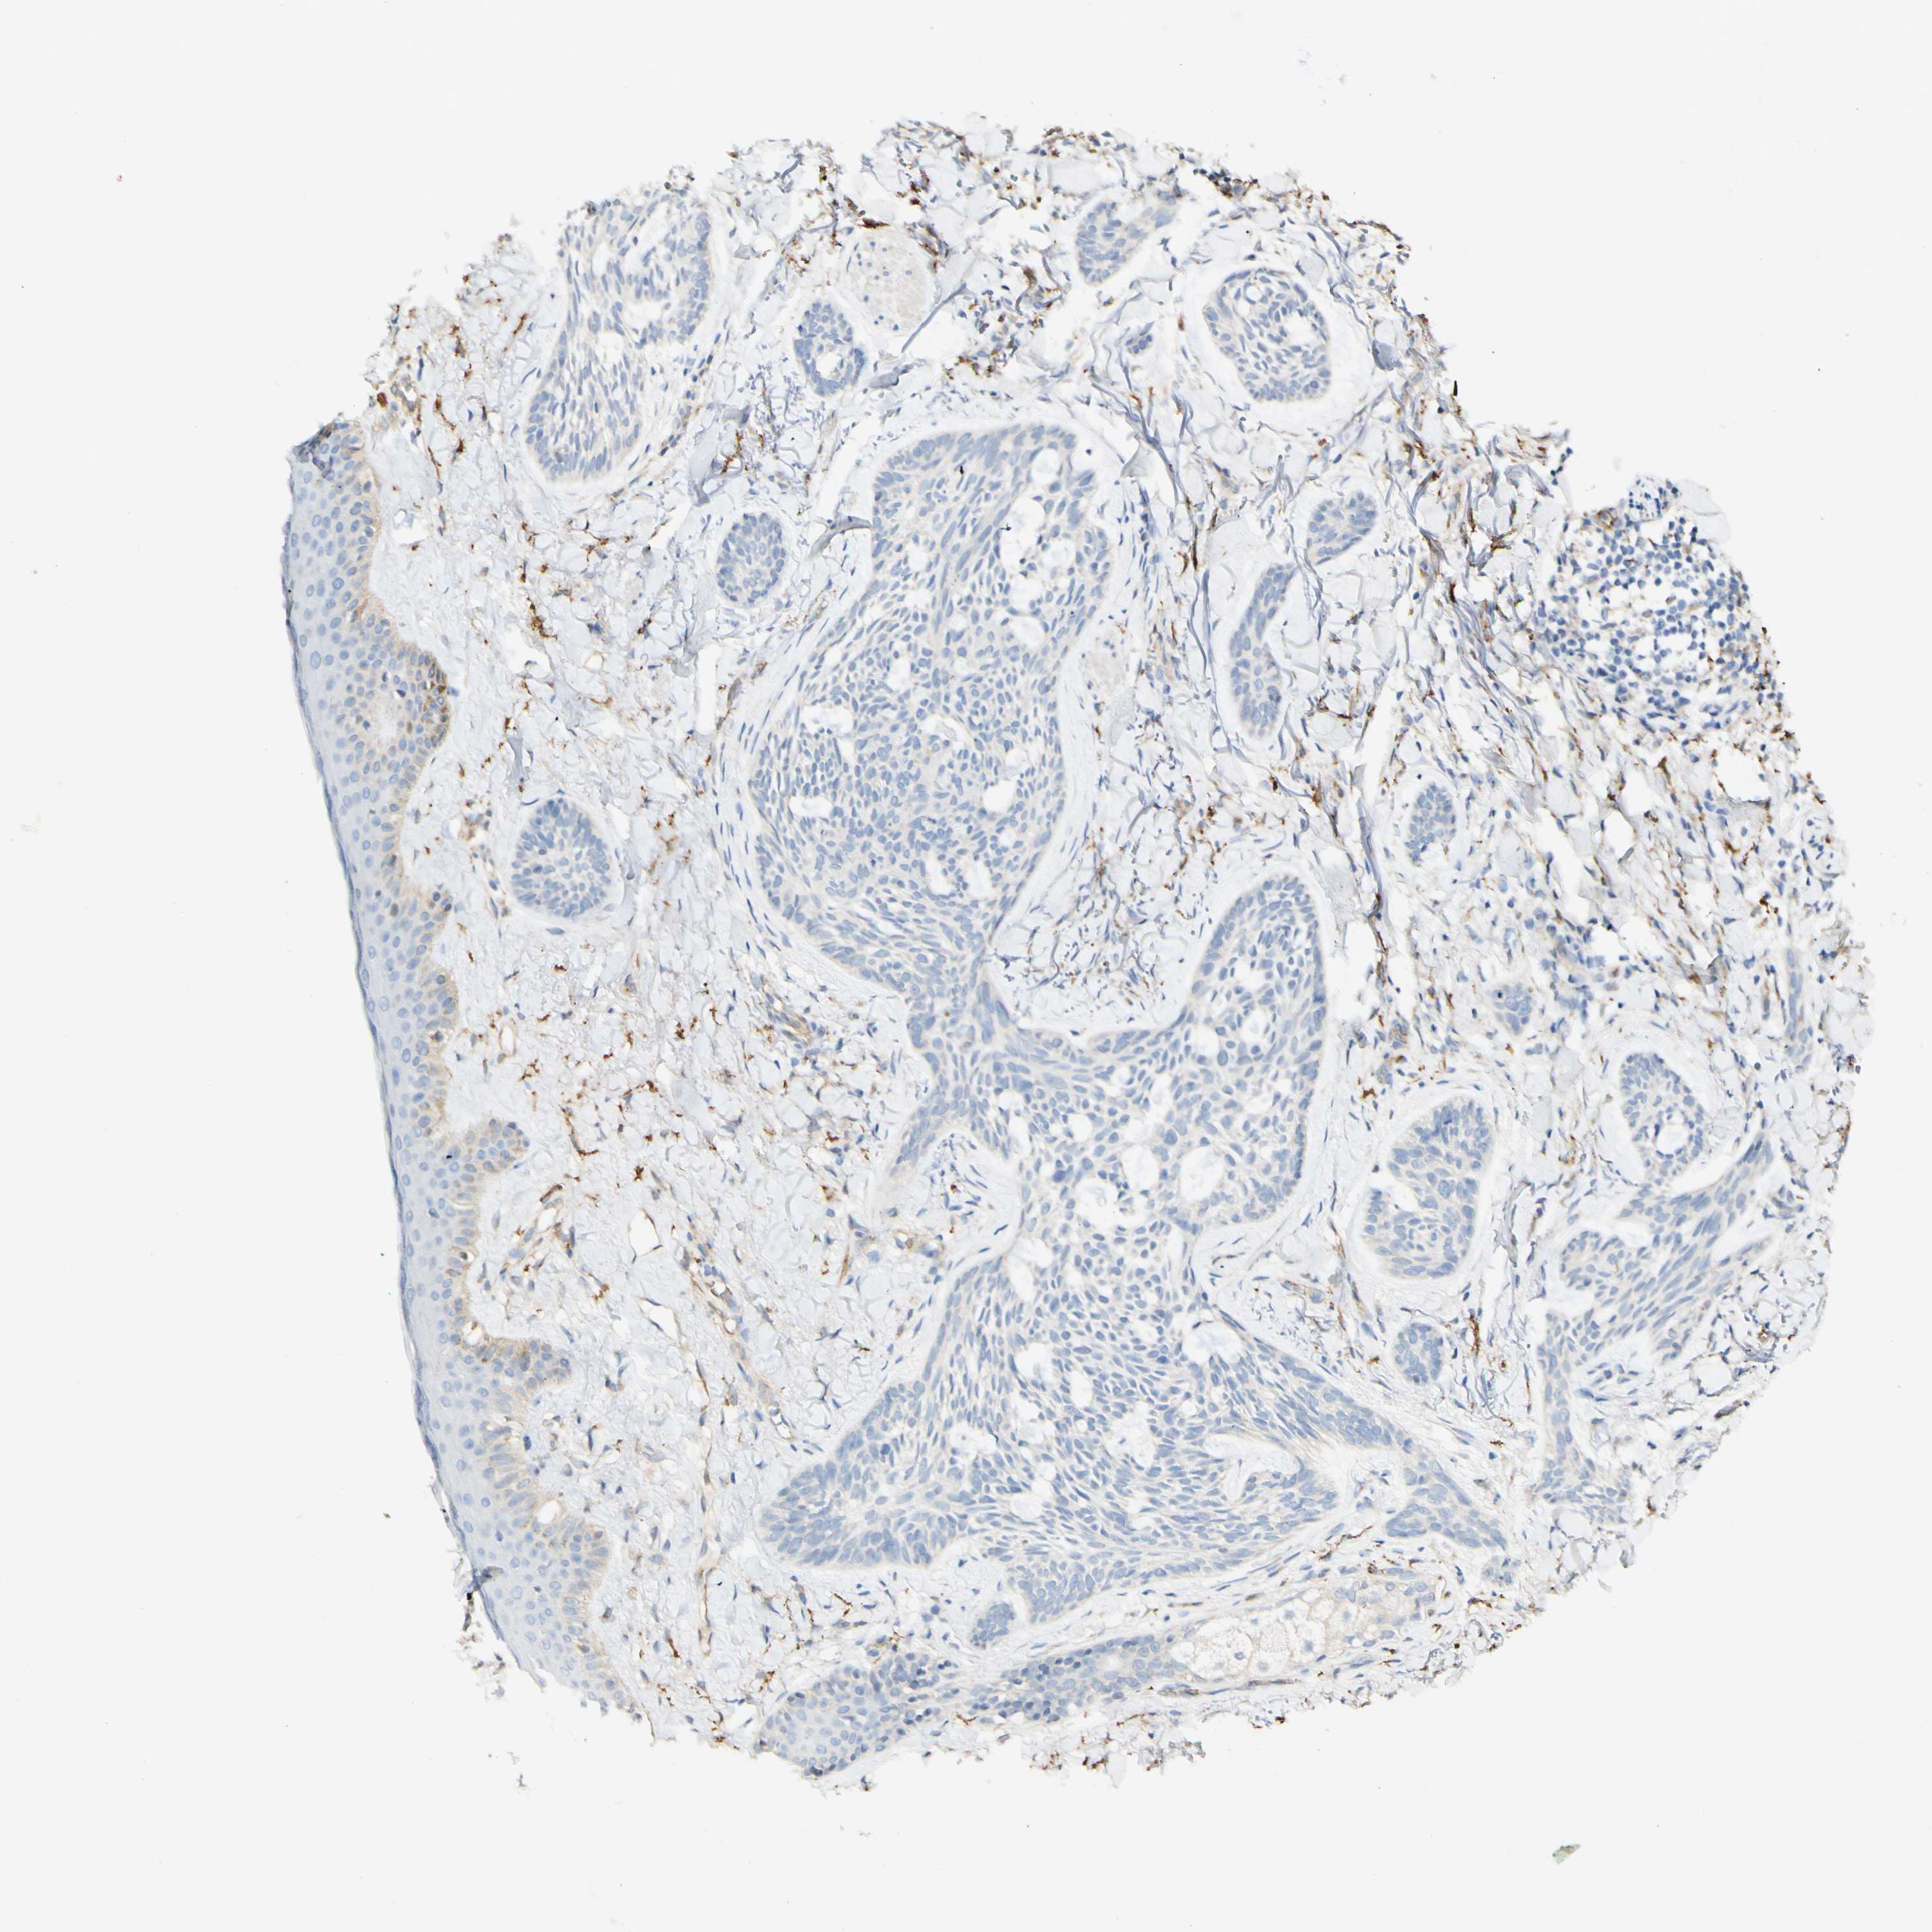

CANCER SKIN CANCER Show tissue menu

SKIN CANCER - Protein expressioni

A mouse-over function shows sample information and annotation data. Click on an image to view it in a full screen mode. Samples can be filtered based on level of antibody staining by selecting one or several of the following categories: high, medium, low and not detected. The assay and annotation is described here.

Antibody staining in the annotated cell types in the current human tissue is reported as not detected, low, medium, or high, based on conventional immunohistochemistry profiling in selected tissues. This score is based on the combination of the staining intensity and fraction of stained cells.

Each image is clickable and will lead to virtual microscopy that enables deeper exploration of all samples and also displays staining intensity scores, fraction scores and subcellular localization as well as patient and tissue information for each sample.

Squamous cell carcinoma, NOS

Adnexal tumor, benign

Basal cell carcinoma